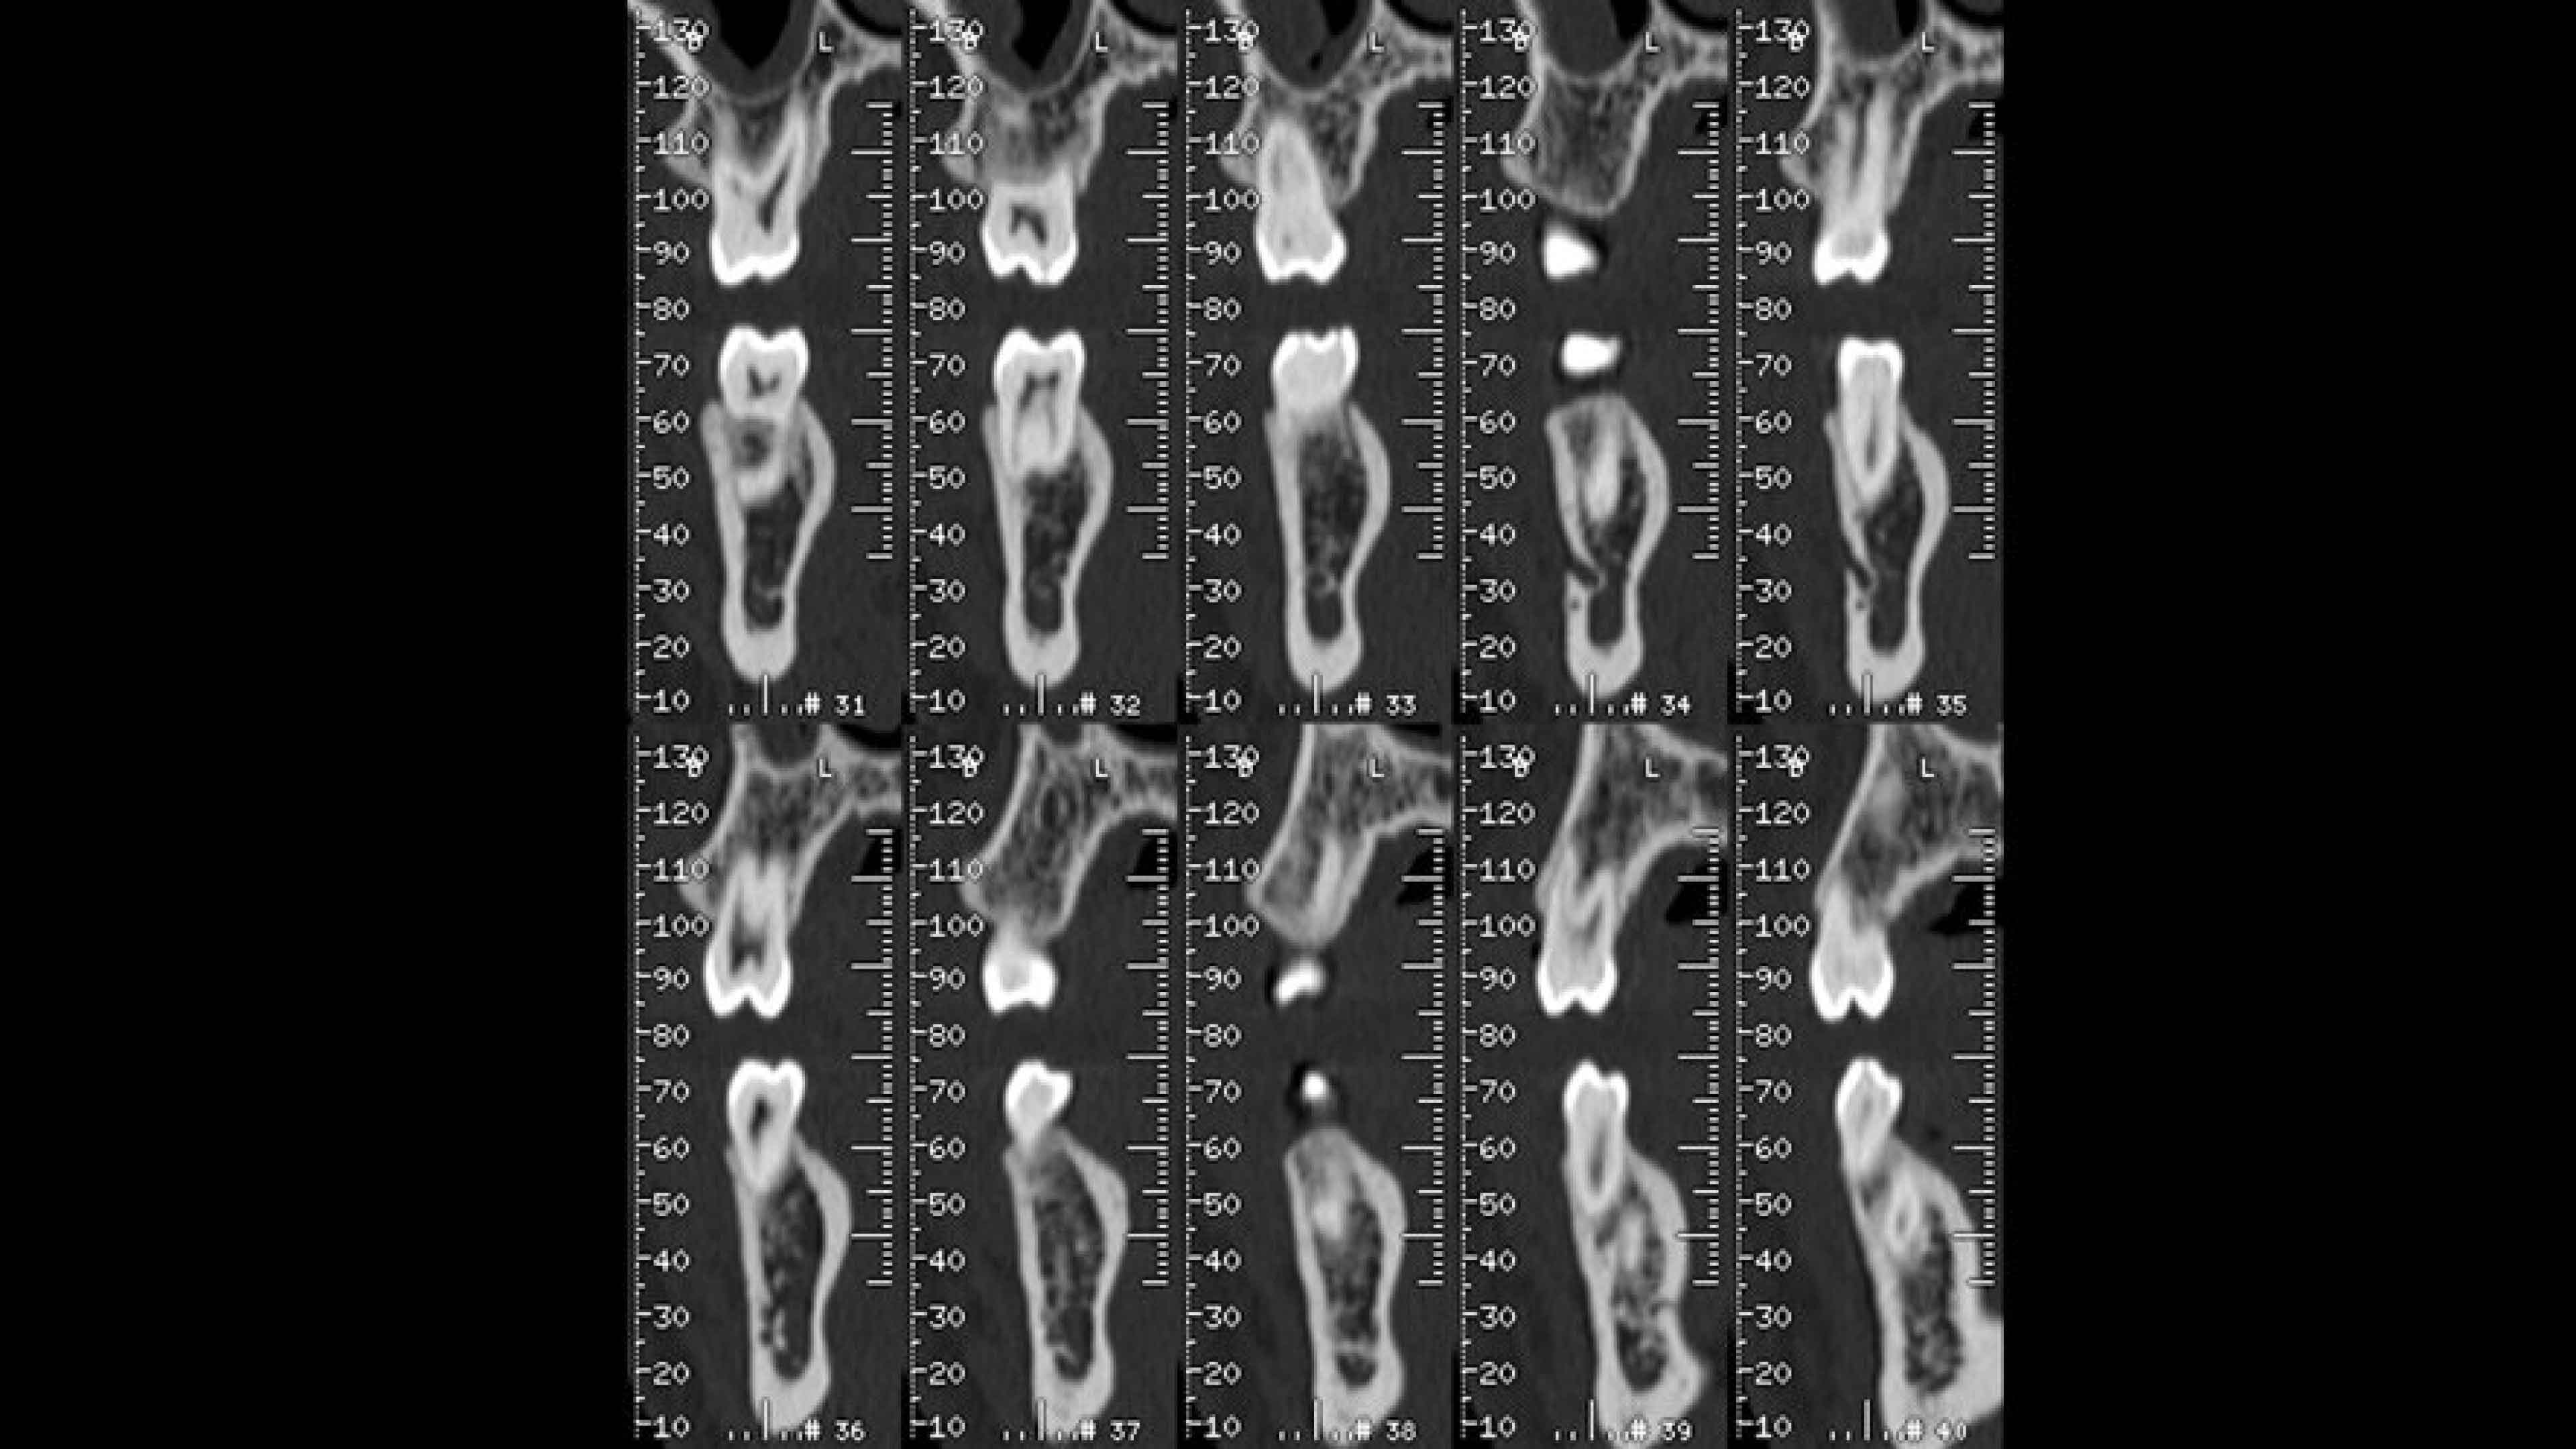

Filming

Film composition is automatic. 𠊊utomatically annotates studies to assist in film interpretation.

• Axial panorex and oblique views remain cross referenced on the screen. Oblique views are generated in real time when the cursor is moved on axial or panorex views. A similar feature exists when the cursor is moved on a panorex or oblique view.

• Filming is automatic at selection of the film key. Parameters can be adjusted through the film menu.

• A mm-scale is printed on the side of oblique and panorex views for direct measurement from film. The entire study is annotated to assist in film interpretation.